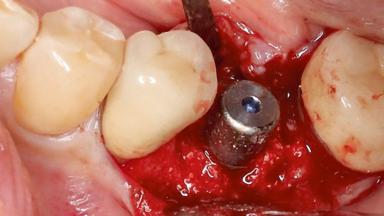

Surgical Management of Peri-Implantitis: Reconstructive Surgical Treatment with Three-Year Follow-up After Treatment

A 70-year-old female patient was referred by her general dentist to the periodontist for assessment and management of an infection associated with implant 36. The general dentist had noted suppuration on probing during examination.